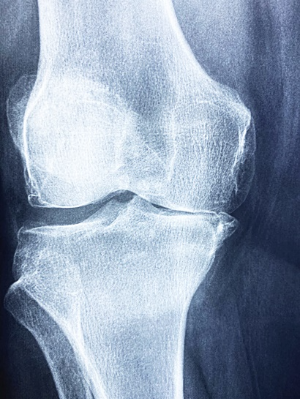

우선, 관절이란 두 개 이상의 뼈가 연결되어 움직임을 가능케 하는 부위입니다. 이는 연골, 인대, 힘줄, 관절낭 등 복합적인 구조로 이루어져 있어, 우리의 일상 움직임과 기능을 원활하게 유지하는 데 중요한 역할을 합니다.

3. 관절 부음

류마티스 관절염은 주로 양쪽의 대칭적인 작은 관절을 표적으로 합니다. 손가락, 발가락의 관절, 손목, 발목, 팔꿈치, 무릎 등이 부어오르고 아프며 따끔거립니다. 이런 부음은 염증으로 인해 관절 주변의 활막이 팽창하고 관절액이 증가하기 때문입니다.